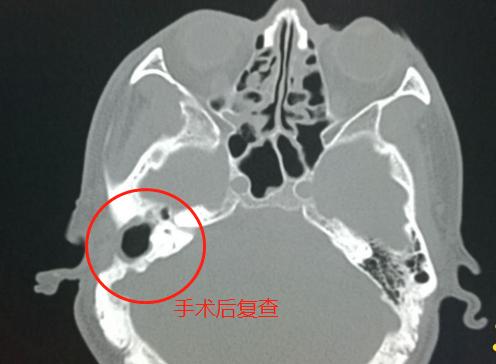

4.胆脂瘤形成,手术后图片——

孩子急性中耳炎听力下降,中耳炎导致的听力下降可以恢复吗

右侧乳突手术后,局部骨质缺损